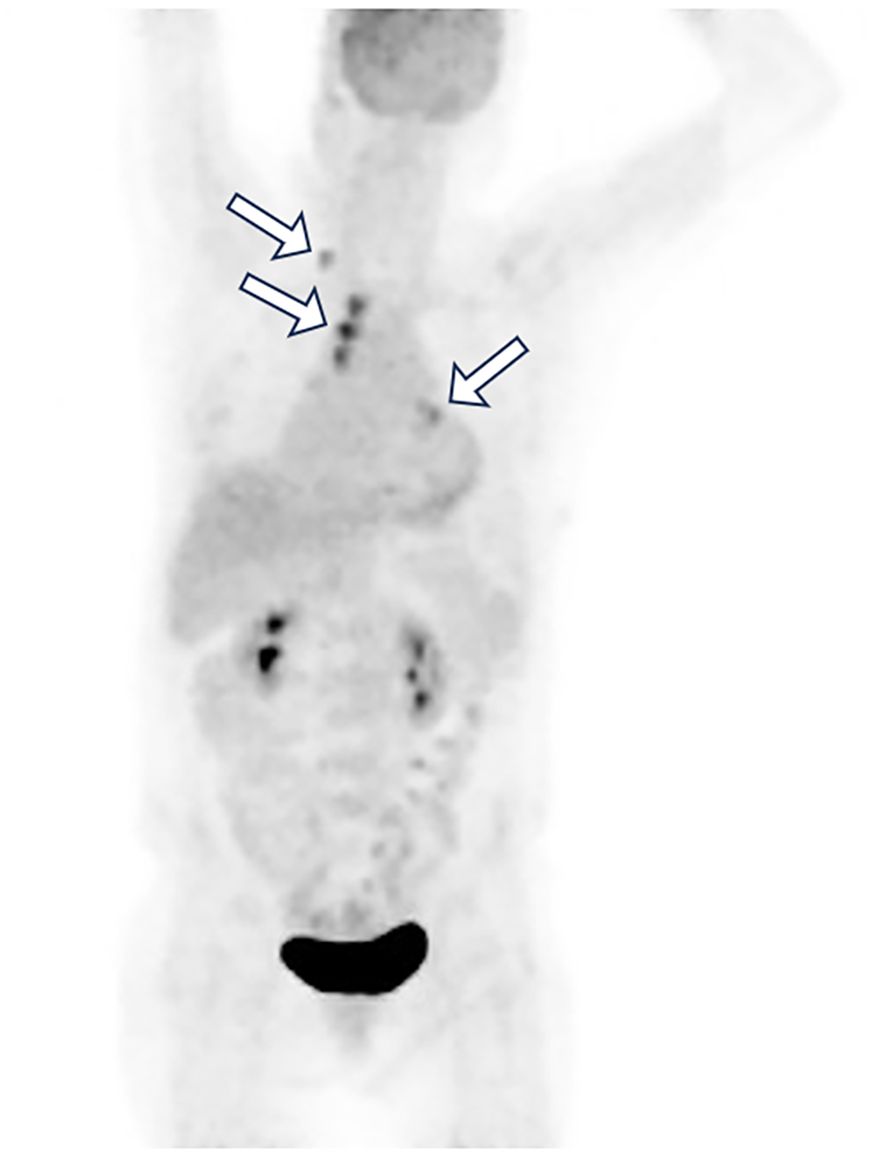

BRAF V600E mutation defines a rare but targetable subset of NSCLC. We report a 70-year-old non-smoking woman with unknown primary lung adenocarcinoma presenting with multistation mediastinal lymph-node metastases and massive malignant pleural and pericardial effusions. Molecular profiling showed BRAF V600E mutation and high PD-L1 expression(TPS 90%, CPS 95). The patient received combined dabrafenib, trametinib, and pembrolizumab with close safety monitoring, achieving rapid tumor control and complete remission by six months with manageable toxicity. This case suggests that early integration of PD-1 blockade with BRAF/MEK inhibition treatment may benefit selected patients and underscores the value of comprehensive molecular and immunohistochemical assessment to guide individualized therapy.